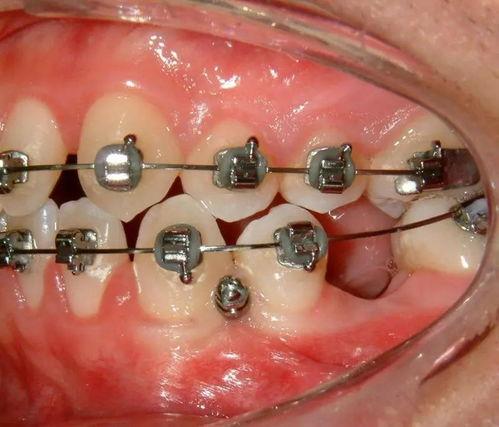

傳統(tǒng)金屬托槽正畸

特點(diǎn):是最常見的正畸方法之一,通過在牙齒上粘貼金屬托槽,利用金屬弓絲施加力量來移動(dòng)牙齒。具有矯正效果可靠、適用范圍廣等優(yōu)點(diǎn)。

矯正過程:一般需要每個(gè)月復(fù)診一次,調(diào)整弓絲的力量和位置。整個(gè)矯正過程通常需要1-3年,具體時(shí)間取決于牙齒的復(fù)雜程度。